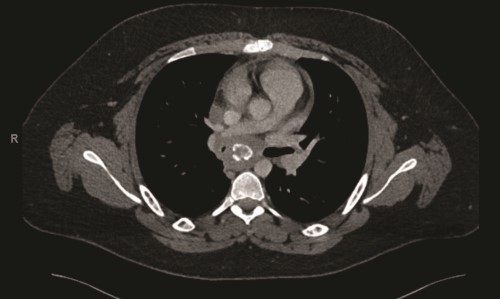

A contrast-enhanced computed tomography (CT) scan of the chest revealed a confluent calcified tissue density mass surrounding the subcarinal, right peritracheal, and anterior mediastinal region, causing significant extrinsic compression of the mid and distal trachea and right main stem bronchus, narrowing of the pulmonary artery, and partial encasement of the azygos vein.

CT of the chest with contrast showed a partially calcified soft tissue mass in the right paratracheal region, extending around the inferior trachea, carina, and proximal mainstem bronchi. The mass measured approximately 8.1 x 6.2 x 7.6 cm.